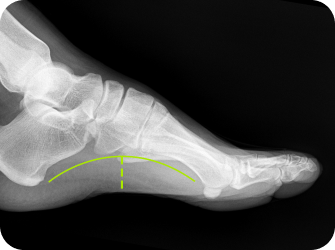

족궁 높이 측정

유연성 평발이 있는 경우에는 평발의 교정이 필수입니다.

특히 거골이 안쪽으로 과도하게 틀어진 경우 6세 이후부터 서서히 그 굳어지기 때문에 6세이후에도 안짱걸음이 지속된다면 반드시 검사가 필요합니다.